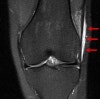

MRI : 장경인대증후군(Iliotibial band syndrome)